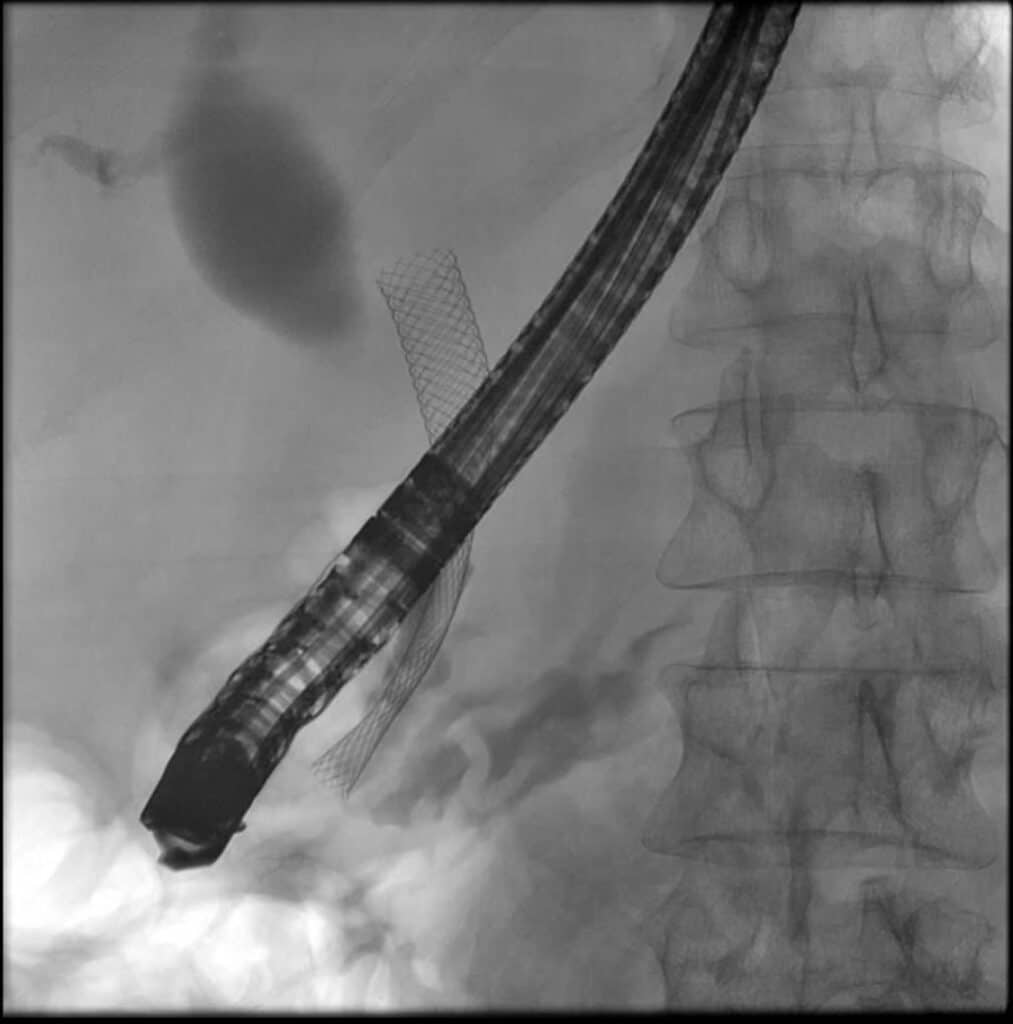

Die Patientin wurde wegen eines schmerzlosen Ikterus vorstellig. Nach sonographischer Beurteilung mit Nachweis eines unklaren Pankreaskopfprozesses mit Doppelgangzeichen wurden EUS und ERCP zur weiteren Diagnostik und Therapie durchgeführt: Endosonographisch sahen wir atrophes Parenchym bei massiv dilatiertem Gangsystem, intraductal stellten sich wandständige papilläre Binnenstrukturen dar; im Kopfbereich wurde zudem eine inhomogen-echoarme Raumforderung abgrenzbar. Umgebend sahen wir vergrößerte Lymphknoten. Bei Nachweis mehrerer „worrisome features“ nach Fukuoka-Kriterien erschienen diese Veränderungen als dringend verdächtig für eine maligne transformierte IPMN. In der Pankreatikographie zeigten sich zudem typische Füllungsdefekte einer MD-IPMN, nach KM-Füllung des DHC erschien eine hochgradige distale Stenose dessen. Der Galleabfluss wurde durch Einlage einer biliären Prothese wiederhergestellt.

Nach CT-morphologischer Korrelation wurde die Patientin einer operativen Therapie zugeführt. Die bereits endoskopisch erhobene Verdachtsdiagnose bestätigte sich auch histologisch: es handelte sich um ein Pankreaskarzinom auf dem Boden einer IPMN.